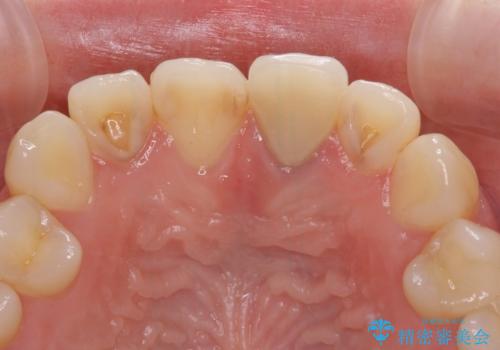

- 前歯のクラウン付近の歯肉が黒く見えることを気にして来院された患者様です。

根管治療を行った後に、オールセラミッククラウンにて補綴することとしました。